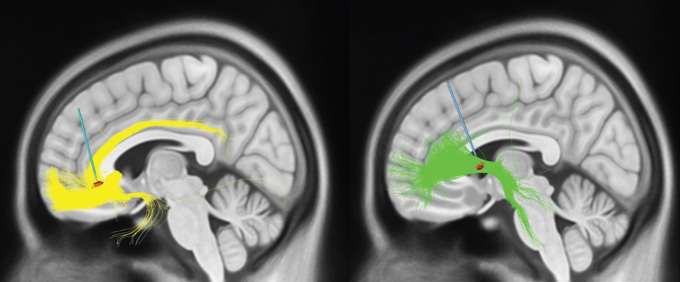

Deep brain stimulation for depression changes signals near the electrodes (red) and signals moving along brain fibers called white matter tracts (yellow and green). The subcallosal cingulum (left) and the ventral capsule/ventral striatum (right) are two current targets.S.A. SHETH AND H.S. MAYBERG/ANNUAL REVIEW OF NEUROSCIENCE 2023

But Mayberg and her colleagues at Mount Sinai aren’t the only people conducting trials on DBS for depression, nor is their target the only one under consideration. Another promising target, called the ventral capsule/ventral striatum, or VC/VS, is more involved in feelings of reward. Stimulating there may be turning up the positive as opposed to dialing down the negative. Its connections to other brain regions are extensive, perhaps even more numerous than the SCC’s.